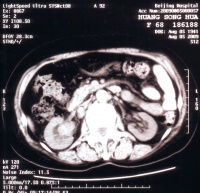

4.CT扫描:CT对肾癌的诊断有重要作用。可以发现未引起肾盂肾盏改变和无病状的肾癌,可准确的测

定肿瘤密度,并可在门诊进行CT可准确分期。有人统计其诊断准确性:侵犯肾静脉91%,肾周围扩散78%,淋巴结转移87%,附近脏器受累96%。肾癌CT检查表现为肾实质内肿块亦可突出于肾实质肿块为圆形,类圆形或分叶状边界清楚或模糊,平扫时为密度不均匀的软组织块,CT值>20Hu,常在30~50Hu间,略高于正常肾实质,也可相近或略低,其内部不均匀系出血坏死或钙化所致,有时可表现为囊性CT值,但囊壁有软组织结节经静脉注入造影剂后正常肾实质CT值达120Hu左右,肿瘤CT值亦有增高,但明显低于正常肾实质,使肿瘤境界更为清晰,如肿块CT值在增强后无改变可能为囊肿结合造影剂注入前后的CT值为液体密度即可确定诊断肾癌内坏死灶肾囊腺癌以及肾动脉栓塞后注入造影剂以后CT值并不增高肾血管平滑肌脂肪瘤由于其内含大量脂肪CT值常为负值内部不均匀增强后CT值升高但仍表现为脂肪密度嗜酸细胞瘤在CT检查时边缘清晰内部密度均匀一致增强后CT值明显升高。